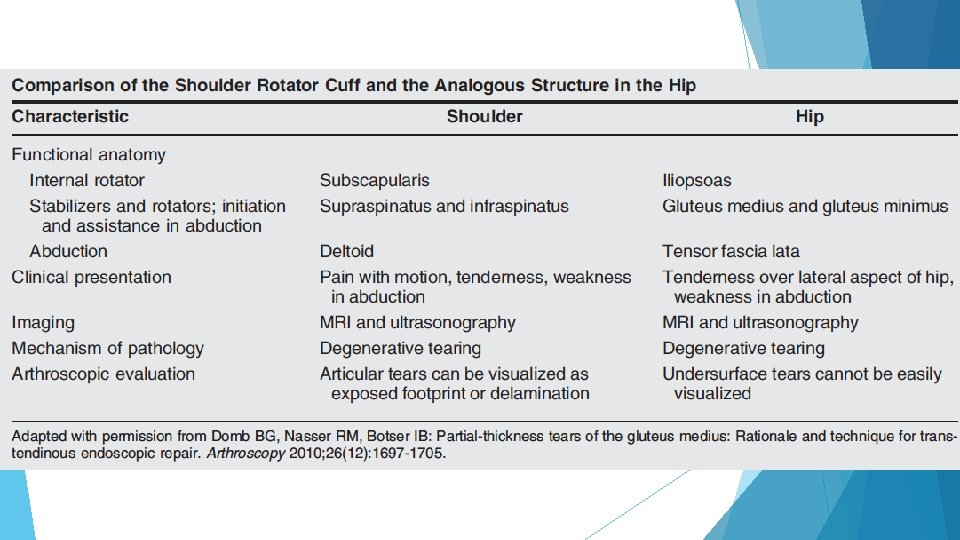

Abductor Tears The Rotator Cuff of the Hip Coaches, Active Parents, Teachers, and other active adults (typically >50 s)

Abductor Anatomy